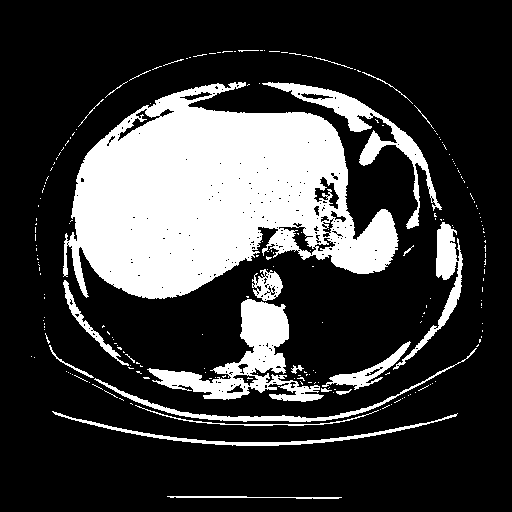

Original NATIVE CT scan (input)

Full window (WL 1023.5, WW 4095 β†’ Low βˆ’1024, High +3071)

Actual HU range: [-1024.0, 3071.0]